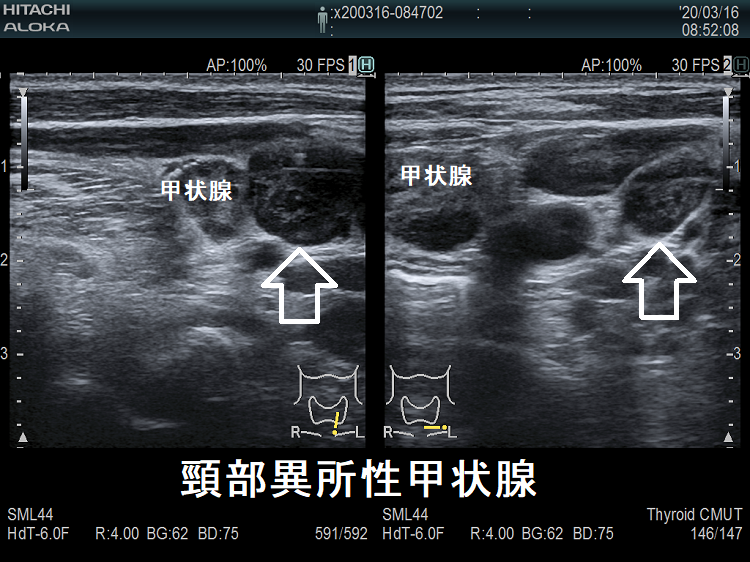

頚部異所性甲状腺

頸部および卵巣内の異所性甲状腺は全体の9.9%です(日臨28: 1784-1789, 1970.)。甲状腺と同エコー輝度の腫瘤が、甲状腺と連続性・非連続性に存在します。I-123 シンチグラフィーで異所性部位に取り込み(集積)を認めます。

橋本病を合併し、副甲状腺と同じ位置にある頚部異所性甲状腺

ケース①

橋本病の異所性甲状腺 超音波(エコー)画像

橋本病を合併し、下極の副甲状腺と同じ位置にある異所性甲状腺。甲状腺本体と同様の破壊性変化を認めます。